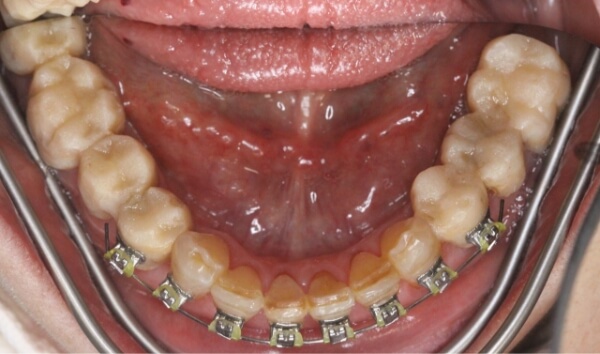

術中

歯は削らずにブラケットを使用して、上下の前歯6本の隙間を閉じる治療を始めることになりました。

矯正装置(ワイヤーと審美ブラケット)をつけた当初は、少し痛みや違和感があったそうですが、歯が動き始めると痛みや違和感は次第になくなっていきました。